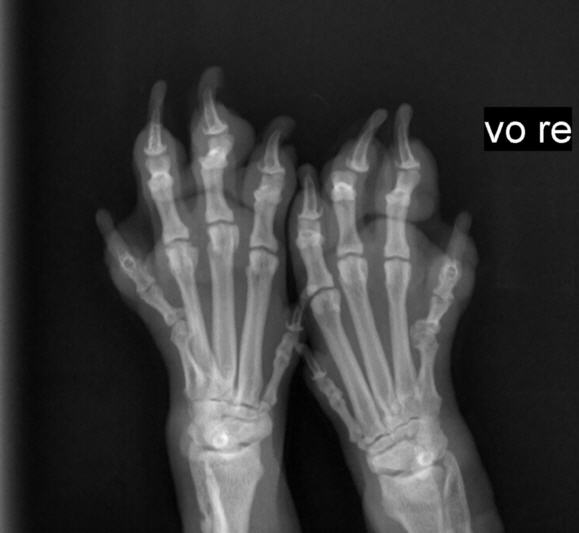

Röntgenuntersuchung Kleintierspezialisten

Röntgen